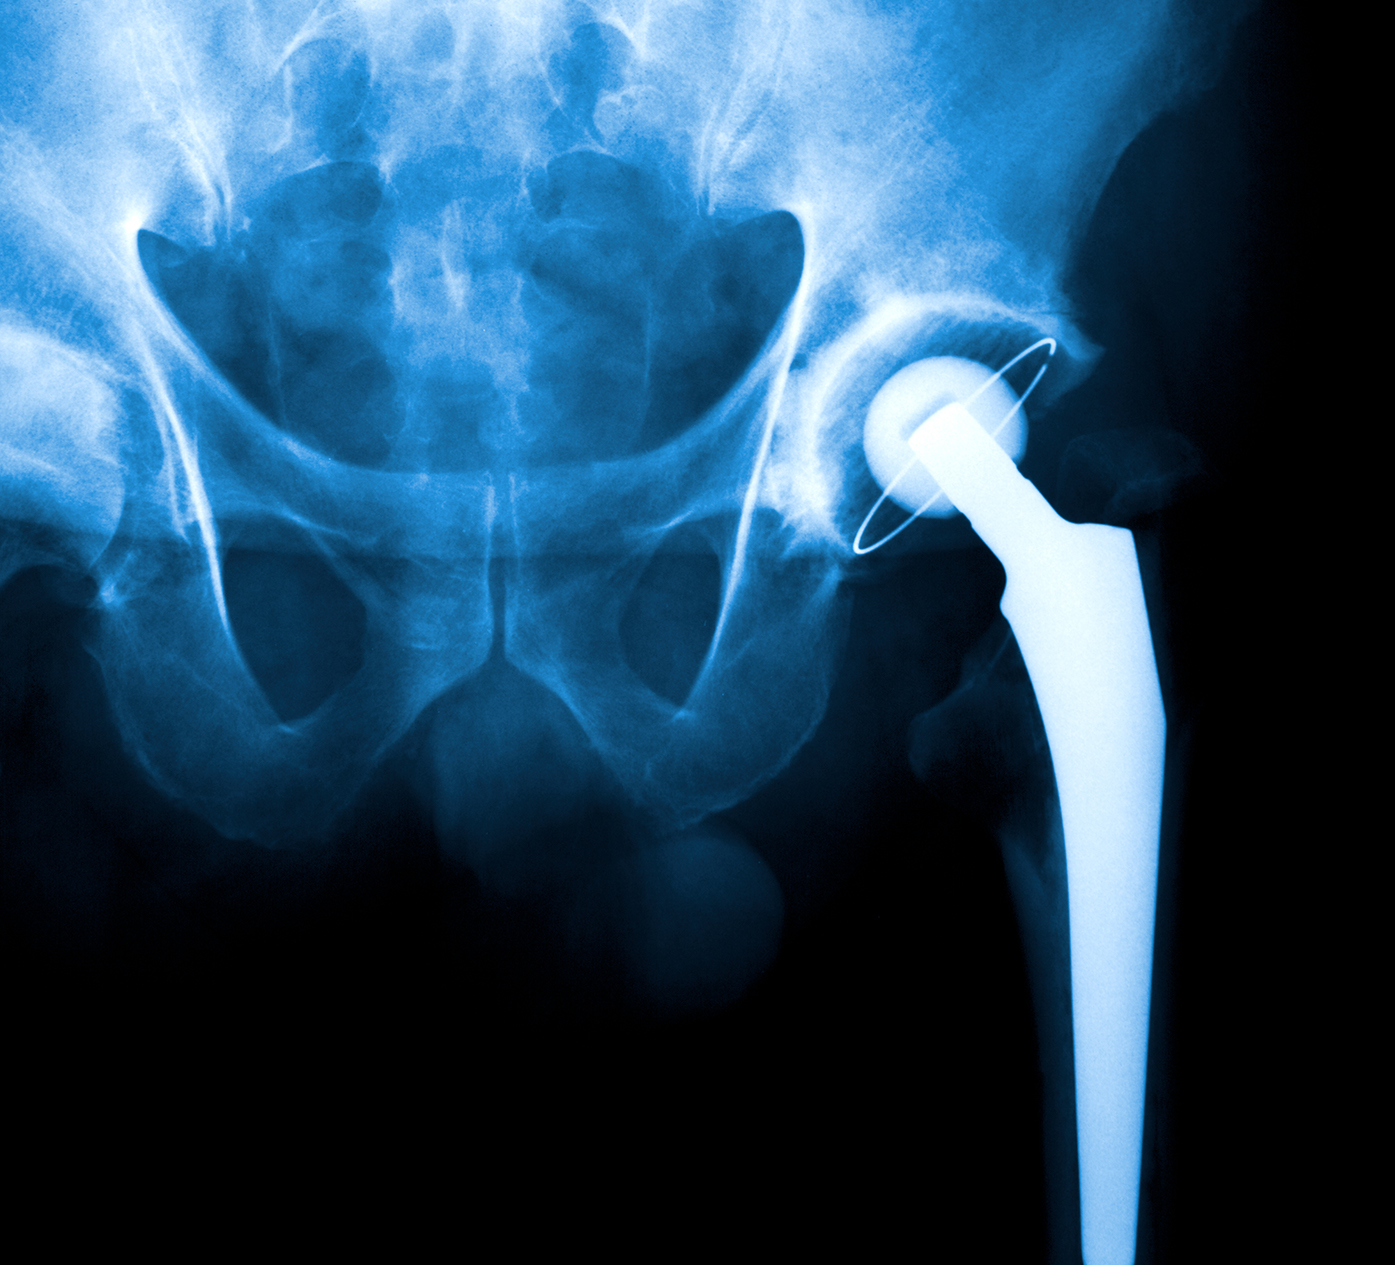

Stryker Hip Replacement Recall List . Please inform users of this urgent. Learn about the latest developments in stryker hip replacement lawsuits involving lfit v40, rejuvenate, abg ii and tritanium devices. Find out the causes, complications, settlements and lawsuits related to the recalls. Please contact your local sales office or your stryker sales representative directly for product replacement and inventory. On 10/15/2021, stryker issued urgent medical device recall notices to customers. Learn about the stryker hip implant recalls involving rejuvenate, abg ii, lfit v40 and accolade tmzf devices. The aaos device recall dashboard provides orthopaedic surgeons with timely recall information that will protect the health and well. Find out if you qualify to file a claim and what injuries are named in the lawsuits. The fda recommends not using or implanting the synovo total hip system, including resurfacing implants, after 2019 due to. Learn about the hip replacement lawsuits filed against stryker and other device makers for complications such as metal poisoning, infection, and nerve damage.

The fda recommends not using or implanting the synovo total hip system, including resurfacing implants, after 2019 due to. Learn about the stryker hip implant recalls involving rejuvenate, abg ii, lfit v40 and accolade tmzf devices. On 10/15/2021, stryker issued urgent medical device recall notices to customers. Find out if you qualify to file a claim and what injuries are named in the lawsuits. Learn about the latest developments in stryker hip replacement lawsuits involving lfit v40, rejuvenate, abg ii and tritanium devices. Please contact your local sales office or your stryker sales representative directly for product replacement and inventory. Please inform users of this urgent. The aaos device recall dashboard provides orthopaedic surgeons with timely recall information that will protect the health and well. Learn about the hip replacement lawsuits filed against stryker and other device makers for complications such as metal poisoning, infection, and nerve damage. Find out the causes, complications, settlements and lawsuits related to the recalls.

Stryker Hip Replacement Recall List Learn about the stryker hip implant recalls involving rejuvenate, abg ii, lfit v40 and accolade tmzf devices. Learn about the hip replacement lawsuits filed against stryker and other device makers for complications such as metal poisoning, infection, and nerve damage. Please inform users of this urgent. Find out the causes, complications, settlements and lawsuits related to the recalls. On 10/15/2021, stryker issued urgent medical device recall notices to customers. The aaos device recall dashboard provides orthopaedic surgeons with timely recall information that will protect the health and well. Learn about the stryker hip implant recalls involving rejuvenate, abg ii, lfit v40 and accolade tmzf devices. Find out if you qualify to file a claim and what injuries are named in the lawsuits. Please contact your local sales office or your stryker sales representative directly for product replacement and inventory. The fda recommends not using or implanting the synovo total hip system, including resurfacing implants, after 2019 due to. Learn about the latest developments in stryker hip replacement lawsuits involving lfit v40, rejuvenate, abg ii and tritanium devices.